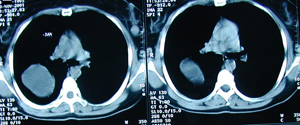

Εικόνα 3α-δ

Αξονική τομογραφία του θώρακος σε διαφορετικά επίπεδα που δείχνει εχινόκοκκο κύστη στο οπίσθιο τμήμα του άνω λοβού και δεύτερη κύστη στο οπίσθιο τμήμα του κάτω λοβού με εικόνα ρήξης.

Α-Β

Γ-Δ